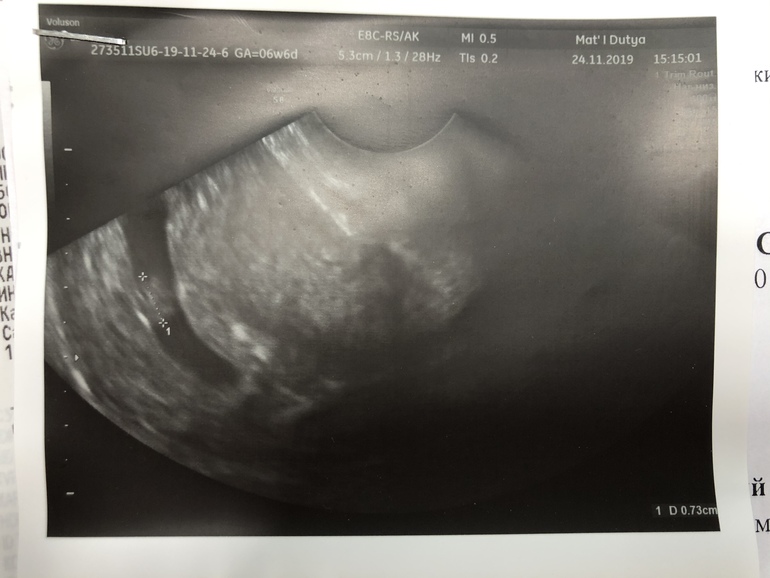

Вчера 24.11.2019 г. наконец-то были на узи и послушали сердцебиение нашего малыша!😍Убедилась, что все развивается хорошо и успокоилась)) даже не сдержалась и расплакалась, какой же это был важный и дорогой для меня момент😭переживала и ждала узи вечность! Мужу я кстати рассказала не как хотела после узи, а неделю назад, потому что уже начал задавать вопросы и просил рассказать что со мной происходит, думал я чем-то больна и не хочу ему рассказывать😅беременности был рад, поддержал и ждал узи вместе со мной, даже зашёл послушать сердечко, но был недоволен, видимо смущался находится там и не совсем понимал что ему показывают )) теперь осталось сдать анализы и 11 декабря на приём к врачу вставать на учёт)) желаю всем такой радости и спасибо всем кто поддерживал меня, очень рада что существует этот добрый и душевный сайт! ♥️

а я сразу поняла, потому что сначала я на картинке не понимала и уже просила сказать скорее и показать, чтобы успокоится, доктор приблизила прям эмбриончик близко-близко и я увидела как маленькая точечка бьется она включила звук и у меня побежали слезы)))